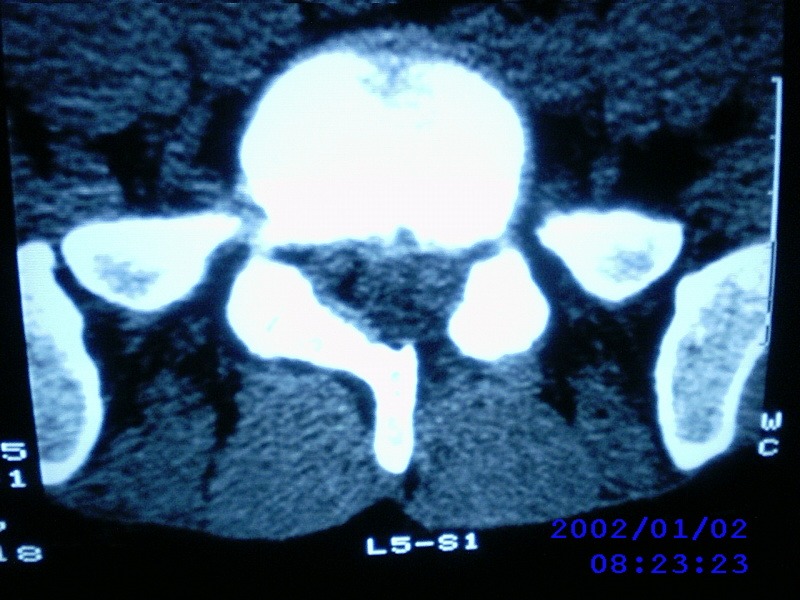

患者,男性,40岁,腰痛伴左下肢疼痛、麻木6年。5年前做过腰椎间盘手术,具体是哪个位置病人记不清了。

我拍的是l4-5、l5-s1

1)l4/5及l5/s1左侧椎板术后改变。2)l5/s1椎间盘突出,l5椎体下缘许莫氏结节。3)l4/5椎间盘膨出并突出。4)l3/4椎间盘膨出。

1)l4/5及l5/s1左侧椎板术后改变。2)l5/s1椎间盘突出,l5椎体下缘许莫氏结节。3)l4/5椎间盘膨出并突出。

1)l4/5及l5/s1左侧椎板术后改变。2)l5/s1椎间盘突出,l5椎体下缘许莫氏结节。3)l4/5椎间盘膨出并突出。4)l3/4椎间盘膨出。支持!